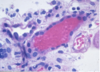

ANAPLASIA

Determines the Prognosis of Wilms tumor

- Pleomorphism, hyperchromatism, abnormal mitoses –> more aggresssive; higher resistance to chemotherapy

- Stage matters also w/ Prognosis*